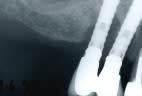

le bruxisme provoque des fractures, et les bactéries, associées à une réponse de l'hote inadaptée, provoquent des périimplantites; un bon p'tit curetage associé à 1 gel antibiotique type parocline répare beaucoup de choses; ci joint un vieux cas très intéressant de 1999, et un an après le traitement indiqué plus haut; la patiente est décédée en 2004 avec ses implants sans plus des soucis; tous mes rares cas de périimplantites ont cédé à ce traitement